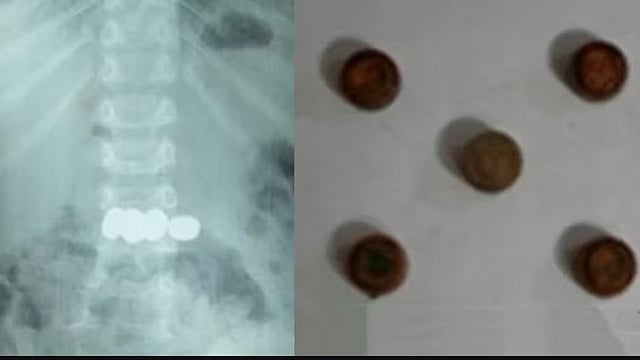

പുറത്തെടുത്ത ബാറ്ററികള്‍

മേപ്പാടി: രണ്ടു വയസ്സുകാരന്‍ വിഴുങ്ങിയ അഞ്ച് കോയിന്‍ ടൈപ്പ് ബാറ്ററികള്‍ എന്‍ഡോസ്‌കോപ്പിയിലൂടെ വിജയകരമായി പുറത്തെടുത്തു. ബത്തേരി മൂലങ്കാവ് സ്വദേശികളുടെ മകനാണ് കളിപ്പാട്ടത്തിലുണ്ടായിരുന്ന ബാറ്ററികള്‍ വിഴുങ്ങിയത്.

കുട്ടി ബാറ്ററികള്‍ വിഴുങ്ങുന്നത് കണ്ടതോടെ വീട്ടുകാര്‍ ആശുപത്രിയില്‍ എത്തിക്കുകയായിരുന്നു. എന്‍ഡോസ്‌കോപ്പിയിലൂടെയാണ് ബാറ്ററികള്‍ പുറത്തെടുത്തത്. ഡോ.മൂപ്പന്‍സ് മെഡിക്കല്‍ കോളജിലെ ഗാസ്ട്രോ എന്ററോളജി വിഭാഗം സ്‌പെഷലിസ്റ്റ് ഡോ.സൂര്യനാരായണയുടെ നേതൃത്വത്തിലായിരുന്നു ബാറ്ററികള്‍ പുറത്തെടുത്തത്. സമയബന്ധിതമായി ചികിത്സ ഉറപ്പാക്കാനായതിനാലാണ് വലിയ അപകടം ഒഴിവാക്കാന്‍ സാധിച്ചതെന്നും കുട്ടിയുടെ ആരോഗ്യനില തൃപ്തികരമാണെന്നും ആശുപത്രി അധികൃതര്‍ അറിയിച്ചു.

ബാറ്ററികള്‍ ആമാശയത്തില്‍ എത്തിയാല്‍ ഉള്ളിലെ അസിഡിക് പ്രവര്‍ത്തനത്തിലൂടെ പൊട്ടാനുള്ള സാധ്യതയുണ്ടെന്നും അങ്ങനെയുണ്ടായാാല്‍ കുടല്‍, കരള്‍ തുടങ്ങിയ അവയവങ്ങളില്‍ ഗുരുതരമായ ക്ഷതം ഉണ്ടാകുമെന്നും ഡോക്ടര്‍മാര്‍ പറഞ്ഞു. ഇത്തരത്തില്‍ കളിപ്പാട്ടങ്ങളുമായി ഇരിക്കുന്ന കുട്ടികള്‍ മുതിര്‍ന്നവരുടെ നിരീക്ഷണത്തില്‍ ആയിരിക്കണമെന്ന് ഡോക്ടര്‍മാര്‍ പറഞ്ഞു. ഡോ.അഖില്‍, ഡോ. അഞ്ജന എന്നിവരും ചികിത്സയില്‍ പിന്തുണ നല്‍കി.